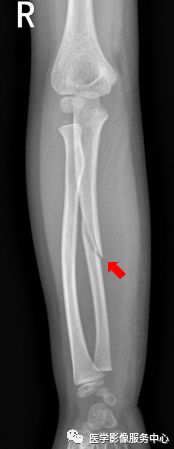

前臂

右侧尺骨中段可见斜形骨折线,骨折端稍分离移位。右侧尺骨中段骨折。